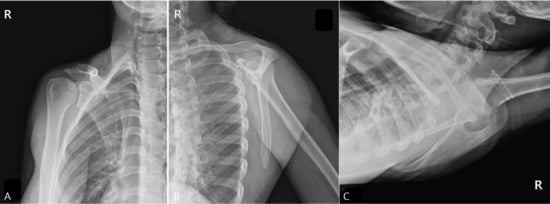

Ultrasonographic Diagnosis and Computed Tomographic Confirmation of a Scapular Body Stress Fracture in an Elite Boxer: A Case Report

Background and Clinical Significance: Scapular stress fractures are exceptionally rare in athletes and are notoriously difficult to diagnose due to their subtle presentation and poor sensitivity on initial radiographs. This case report describes the diagnostic challenge of a scapular body stress fracture in an elite boxer who initially presented with wrist pain. Case Presentation: A 19-year-old right-hand-dominant female elite boxer presented with a three-month history of bilateral wrist pain. Initial examination and MRI were consistent with a triangular fibrocartilage complex (TFCC) injury. Despite conservative management, her symptoms persisted, and she subsequently developed mechanical right shoulder pain and a sensation of instability. Physical examination revealed scapular dyskinesis, with a positive push-up test and weakness on punch protraction. Plain radiographs of the scapula were unremarkable. Point-of-care musculoskeletal ultrasound (MSK US) identified a cortical irregularity at the medial scapular border. A subsequent computed tomography (CT) scan obtained at three-month follow-up definitively confirmed a stress fracture at this site. Treatment focused on scapular stabilization via prolotherapy and activity modification, leading to symptomatic resolution and a successful return to sport. Conclusions: This case underscores the importance of evaluating the entire kinetic chain in athletes presenting with focal complaints. It demonstrates the utility of MSK US as an effective initial screening tool for cortical stress fractures and highlights the necessity of CT for definitive confirmation. Clinicians should maintain a high index of suspicion for scapular stress injuries in overhead athletes with unexplained shoulder dysfunction. Full article

Figure 1